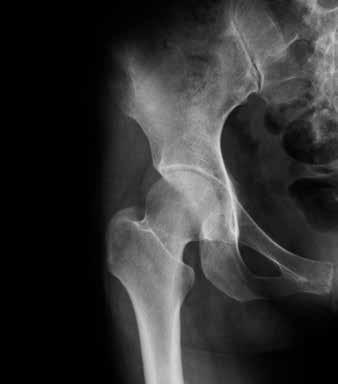

Articolazione artrosica dell’anca

Articolazione sana dell’anca

Nel tempo l’artrosi si sviluppa in modo molto diverso da persona a persona. Può colpire una o più articolazioni. Allo stadio iniziale, poi, è difficile prevedere se ci si deve aspettare dolori, rigidità o limitazioni motorie. A volte gli esami radiologici evidenziano alterazioni marcate, ma la persona colpita se ne accorge appena nella sua vita quotidiana. Viceversa, è possibile che una persona avverta forti dolori senza che la radiografia evidenzi degenerazioni importanti.

A tutt’oggi non è ancora chiaro quali siano i fattori che influenzano l’entità dei disturbi. È importante sapere, però, che una diagnosi di artrosi non vuol dire automaticamente che bisogna aspettarsi forti limitazioni in futuro.